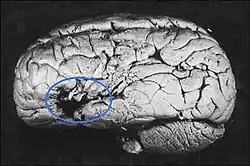

Was Broca einen Platz in der Medizingeschichte sichert, ist seine 1861[6] publizierte Entdeckung des Sprachzentrums im Gehirn, heute bekannt als Broca-Areal, gelegen im dritten Gyrus (Gehirnwindung) des Frontallappens der linken Gehirnhälfte.

Er studierte um das Jahr 1860 Patienten mit einer Aphasie (Sprachstörung mit Verlust der Fähigkeit, Wörter hervorzubringen oder zu verstehen[7]). Sein erster Patient namens Leborgne im Pariser Hôpital Kremlin-Bicêtre konnte nur noch die Silbe ‚Tan‘ aussprechen, weswegen er den Spitznamen „Tan“ erhielt. Das Sprachverständnis dagegen schien nicht beeinträchtigt zu sein: Er war durchaus noch in der Lage, ihm gestellte Fragen zu verstehen. Durch prosodische Artikulation verschiedener Betonungsmuster, Tonhöhen und Aneinanderreihungen dieser einen Silbe versuchte „Monsieur Tan“ die Fragen zu beantworten. Die Autopsie und Untersuchung des Gehirns durch Broca ergab, dass ein Teil der linken Gehirnhälfte zwischen dem Frontallappen und dem Temporallappen eine neurosyphilitische Läsion aufwies. Er berichtete 1861 auch über einen weiteren Patienten, der ebenfalls einen fast völligen Sprachverlust (von Broca „Aphemia“ genannt)[8] erlitten hatte.

Broca folgerte daraus, dass diese Stelle maßgeblich an der Sprachproduktion beteiligt sein müsse. Aus Brocas Befunden entstand die Vorstellung der Lateralisation, also der „asymmetrischen Repräsentation bestimmter Funktionen im Gehirn“.[9]

Das Broca-Areal ist einer von mehreren Bereichen im Gehirn, die zusammen das Sprachzentrum bilden: Während das Wernicke-Zentrum (benannt nach Carl Wernicke) dem Verstehen von Sprache dient, steuert das Broca-Areal maßgeblich die Erzeugung (Motorik) der Sprache.